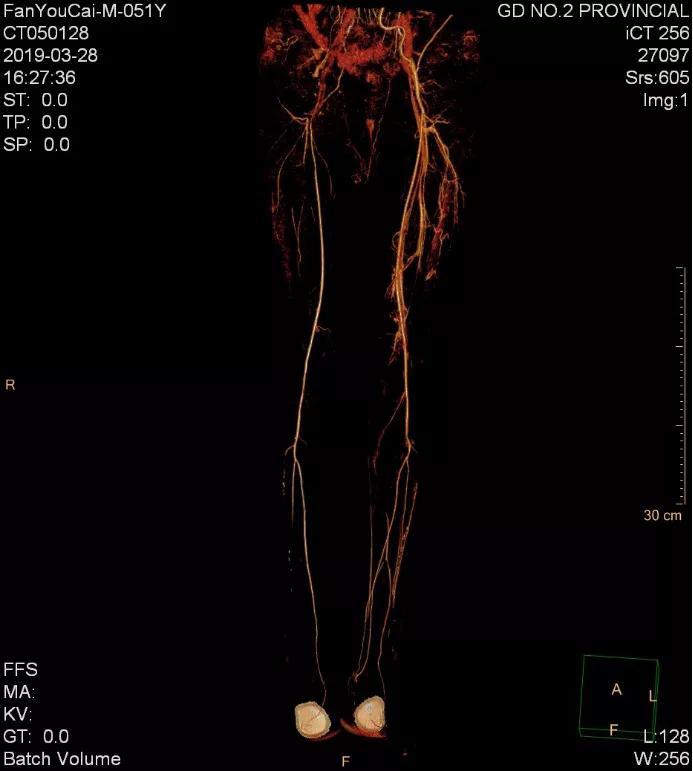

经过系统检查,老樊被确诊为肾下腹主动脉闭塞症。

“根据影像显示,患者主动脉自肾动脉以下完全闭塞,双侧髂动脉完全闭塞,右侧股动脉起始部完全闭塞,双下肢缺血严重,随时面临截肢的风险。”李立恒说。